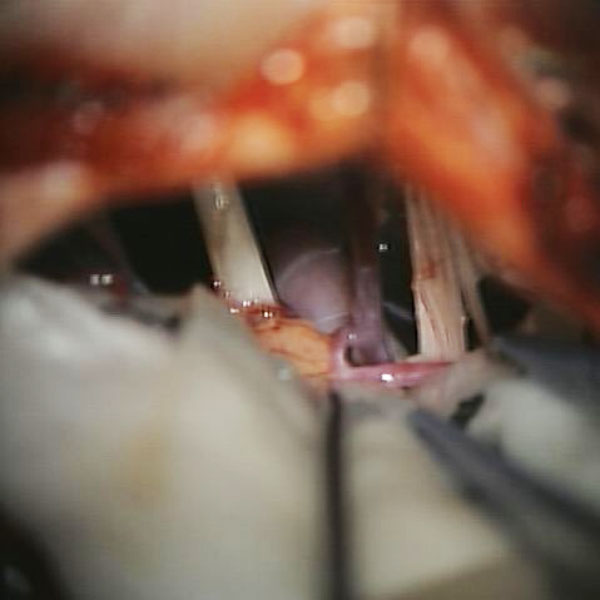

手術中

処置前